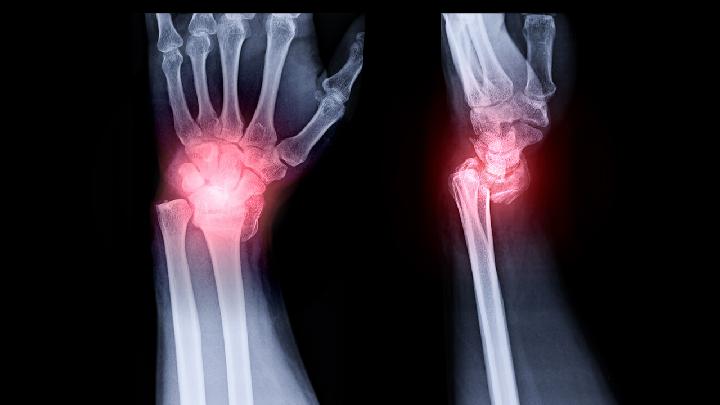

膝关节炎是以膝关节骨及软骨、滑膜为主要改变的疾病,多见于中老年人,特别是女性体胖者,且随着病情的发展症状逐渐加重。本病常因慢性劳损、关节面受力不平衡、关节内紊乱、膝关节不稳或受凉、潮湿、劳累、感染、创伤尤其是外伤后未及时治疗或治疗不当等引起。

关节炎是指由炎症、感染、创伤或其他因素引起的关节炎性病变,关节过度的疲劳和人们的膳食不均衡照成酸性体质会导致关节炎,关节炎可发生于全身各个关节,最容易发生于较大的膝关节、髋关节、脊柱等,下面是膝关节关节炎症状: